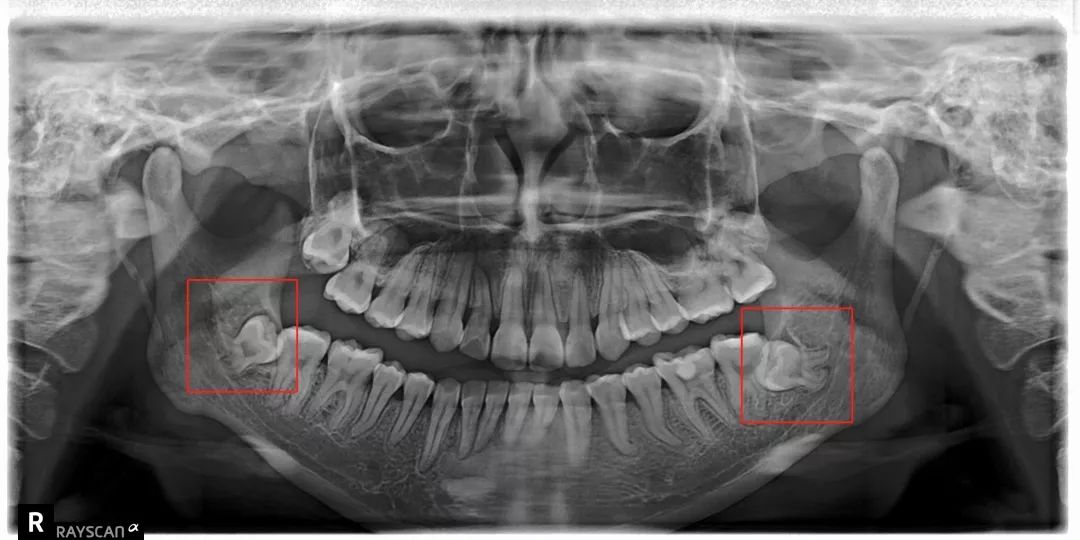

比方说像树根一样长出很多「根」

扎根在骨头里,死死抓住

还有一部分智齿长期发炎

可能会跟我们的骨头黏连

拔出来的时候可能带出来一块骨头